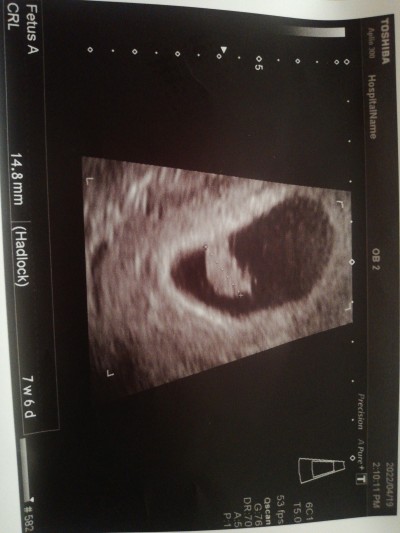

Kızlar ben bugün doktora gittim normalde 8 hafta 5 gün ilene doktor bana 7 hafta 5 günün doldu dedi ama kalp atışını duydum çok mutluyum ama oruç için bana bir fikir verir misiniz tutup tutmamakta ama sabah bulantıları var ve öğleden başlayan baygın baygın geziyorum oruç tutmama rağmen sizde fikir verseniz çok mutlu olurum

Gebelik haftası 7 hafta 5 gün